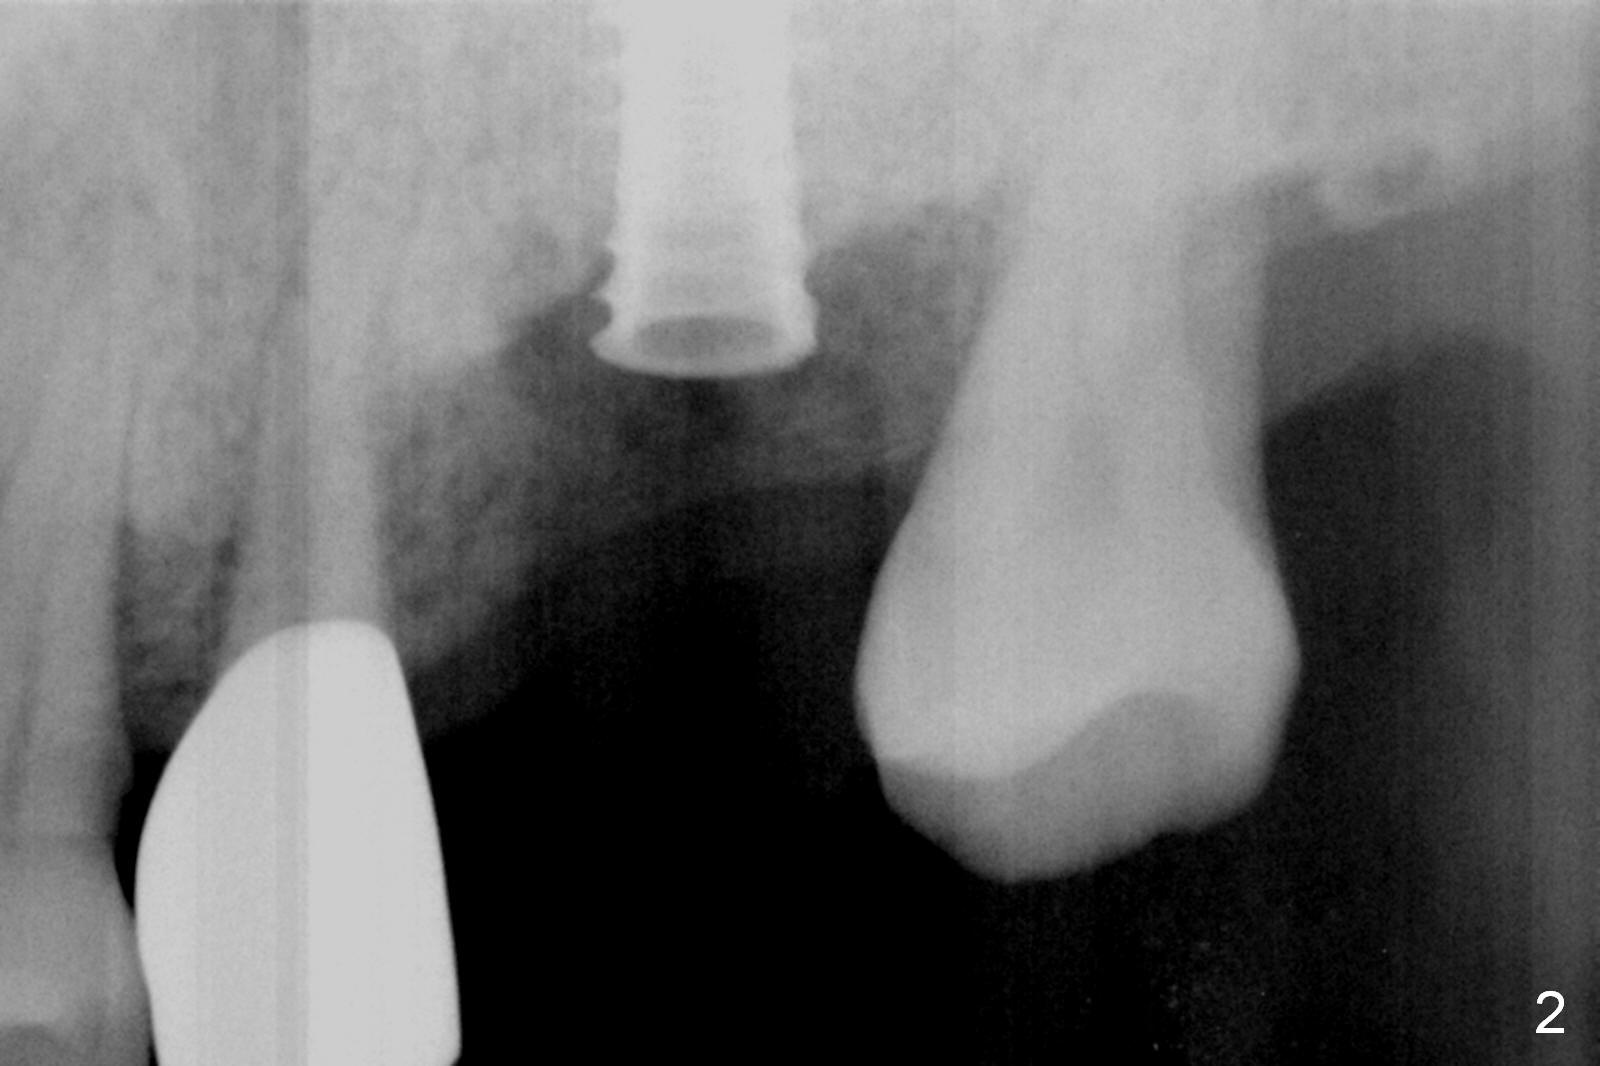

Preop exam show that the tooth #14 appears to be more severe than #18. When the former is extracted with forceps (not so easy), the mesial portion of the mesiobuccal root splits. The latter may be the reason for discomfort and one of the outcomes of advanced peridontitis. The septum is wide enough to use 4.3 mm Magic Drill (MD) following 1.6 mm pilot drill and Marking bur. A 5x13 mm IBS implant is placed apical to the mesial and distal crest and coronal to the septum (Fig.2,3). Insertion torque is ~ 35 Ncm. A 6.0x5.7(4) mm pair abutment is chosen over a 6.5 mm one, because the implant is placed somewhat distally (Fig.4,5). If the implant were placed more apically, the 4 mm cuff would be short for restoration. Allograft and autogenous bone harvested from the MD is placed around the coronal portion of the implant and the abutment cuff (*). Acrylic is spread around the abutment to hold the bone graft in place (without trimming).

The amount of the bone graft mesial and distal the implant seems to reduce 3 and 4 months postop, respectively (Fig.6,7 arrowheads). When the acrylic is cut off 4 months postop, the bone graft is loose. The gingiva is unhealthy. The abutment and implant are loose. A healing abutment is placed (5x4 mm). The implant is torqued to 35 Ncm 6 months postop with the healing abutment reapplied. The patient will return for follow up nearly 9 months postop. A larger healing abutment will be used if the implant is stable. Two weeks later, use a smaller restorative abutment for easy impression. In fact the implant is unstable with #15 mesial shift due to abnormal occlusion with #17 (Fig.8). Bone density around the implant is low (* in Fig.9 (PA), 10,11 (CT sagittal, coronal sections)). A healing screw is placed for self healing. A 2nd option is to remove the implant (Fig.12), BEB (Fig.13) and place the implant deeper (Fig.14) or larger one (5.5-6.5x13 mm). The 3rd option is to place larger and longer implants (Fig.15 (tapered), 16 (cylindrical)). The implant access has partially closed 14 months postop, but there is a small buccal opening with sanguine exudate. Incision reveals severe bone loss around the implant; the mobile tooth #15 is extracted (Fig.17). After debridement and irrigation with normal saline, Vera Graft (Fig.18 *) and Collagen plug are placed with periodontal dressing.